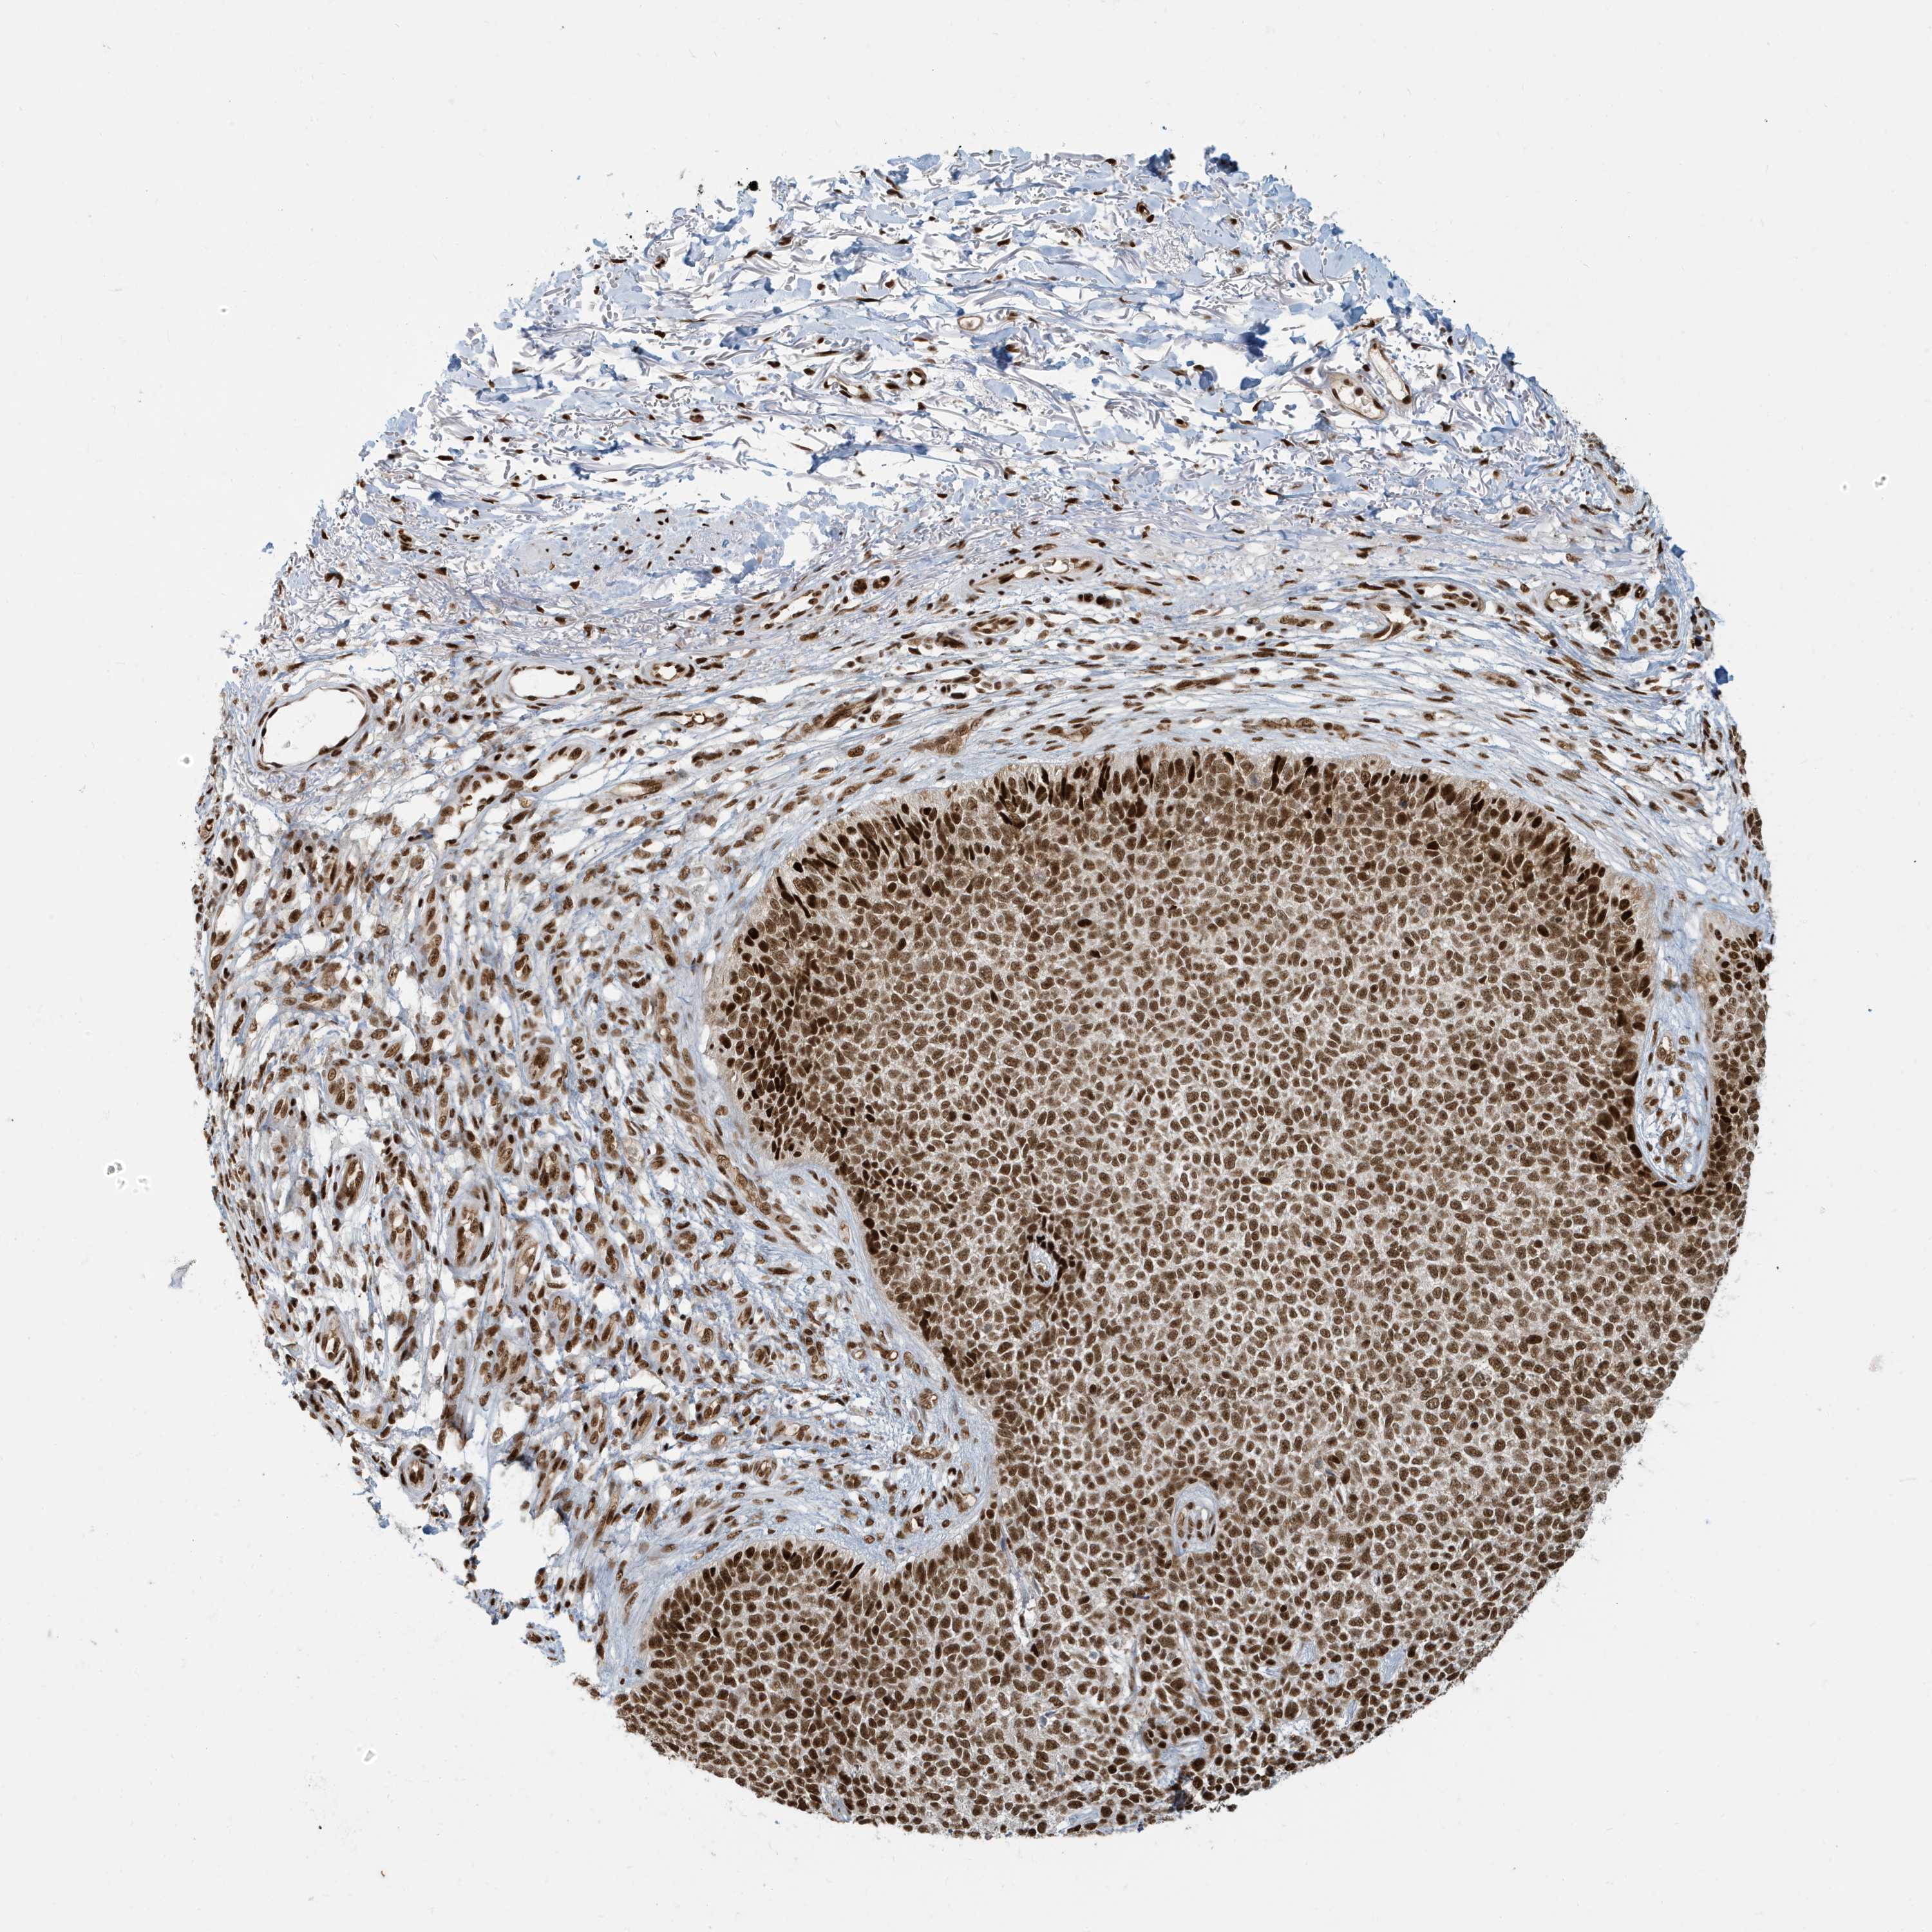

Basal cell and squamous cell cancer

SKIN CANCER - Protein expressioni

A mouse-over function shows sample information and annotation data. Click on an image to view it in a full screen mode. Samples can be filtered based on level of antibody staining by selecting one or several of the following categories: high, medium, low and not detected. The assay and annotation is described here.

Antibody stainingi

Antibody staining in the annotated cell types in the current human tissue is reported as not detected, low, medium, or high, based on conventional immunohistochemistry profiling in selected tissues. This score is based on the combination of the staining intensity and fraction of stained cells.

Each image is clickable and will lead to virtual microscopy that enables deeper exploration of all samples and also displays staining intensity scores, fraction scores and subcellular localization as well as patient and tissue information for each sample.

Antibody HPA030762

Staining

Medium

Intensity

Moderate

Quantity

75%-25%

Location

Nuclear

Squamous cell carcinoma, NOS